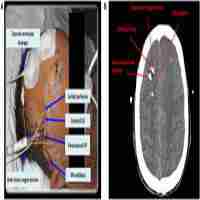

| Abstract | Background: Hyponatremia develops in approximately a third of patients with aneurysmal subarachnoid hemorrhage (SAH). Studies have been conflicting about the association between hyponatremia and cerebrovascular spasm (CVS). Aims: To investigate whether hyponatremia can signal the onset of CVS. Settings and Design: Retrospective chart review of all patients with SAH treated at a tertiary-care university hospital from January to May 2002. Materials and Methods: 106 patients were included in the study. Serum sodium levels were recorded from days 1 to 14 of hospitalization. Hyponatremia was defined as serum sodium level 4 meq/l from the admission sodium level. The presence of CVS was determined by transcranial doppler sonography. Patients were assigned to one of four groups based on the presence or absence of CVS and hyponatremia. Statistical Analysis: Student's t-test was used for comparison of means. A logistical regression model was constructed and odds ratios (OR) were calculated. Results: 41 patients developed hyponatremia and 44 developed CVS. Among the 41 with hyponatremia, 22 (54%) had evidence of CVS, whereas among the 65 patients without hyponatremia, 22 (34%) had evidence of CVS ( P =0.023). Among those with hyponatremia, the mean sodium drop was 7.9 meq/L in those with CVS compared to 7.0 meq/L in those without CVS ( P = 0.068). More than half of those with hyponatremia and CVS (13/22) developed hyponatremia at least a day before CVS was diagnosed. Conclusion: In patients with SAH, hyponatremia is associated with a significantly greater risk of developing CVS and may precede CVS by at least one day. |